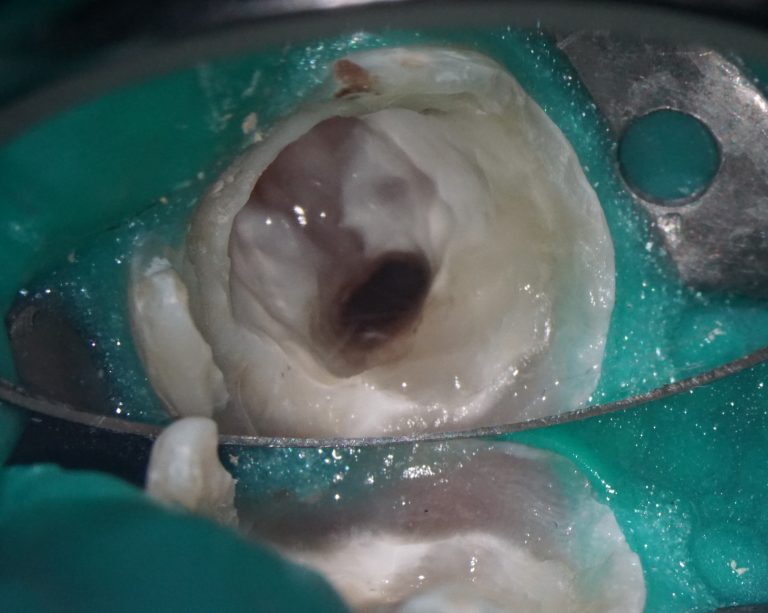

Task: Plan the implant treatment for the replacement of teeth 16 (Universal 3) and 17 (Universal 2), reduce the time required for surgical template fabrication, and improve the accuracy of its fit. Using the “STL” module of Diagnocat, it is possible to create a 3D reconstruction of cone-beam computed tomography (CBCT) and virtual models of templates. To achieve this, intraoral scan data is uploaded into the module, and a suitable CBCT is selected for merging.

Problem:In some clinical cases, it’s difficult to ensure the required accuracy in merging intraoral scanning and CBCT.